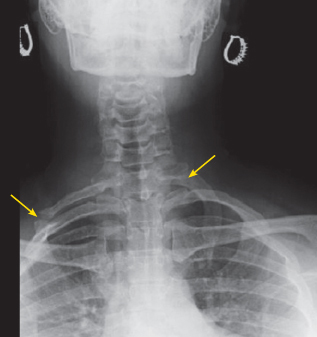

What is this condition? What is it caused by?

Winging of scapula

Long thoracic nerve injury